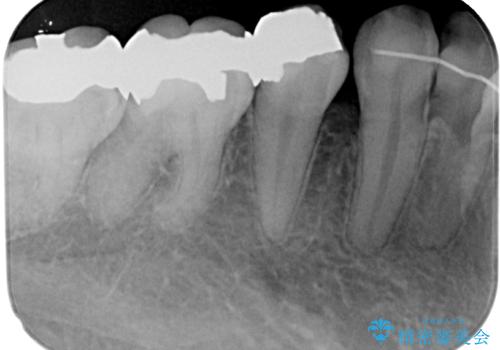

- 当院にて矯正治療を終えた患者様で銀歯を白くしたいとのことで来院された患者様です。神経の反応を確認し詰め物の範囲も大きいためフルジルコニアクラウンにて治療を行うことにしました。

拡大鏡視野下でメタルインレー、虫歯を除去しフルジルコニアクラウンに適した形に整えました。

歯と歯茎の間に圧排糸と言われる糸を入れてシリコーン印象材にて型どりをしました。